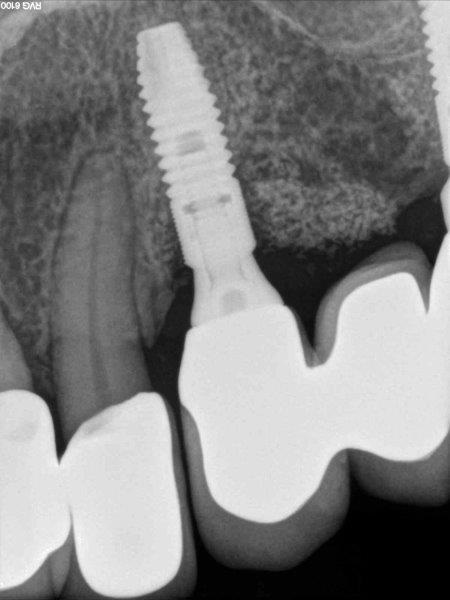

A 55-year-old patient with no medical history was referred for suspected periimplantitis affecting the implant on #11. Peri-implant probing and preoperative periapical X-ray examination confirmed the diagnosis of peri-implantitis, suggesting the presence of a large bone defect on the buccal side (Figs. 4 and 5).

Because of its limited ability to prove a detailed view of the three-dimensional anatomical structures, periapical X-ray examination may not provide full information about important parameters such as alveolar bone thickness, anatomy, size, extension and location of bone defects. To overcome this limitation, clinicians must cross-correlate the data from X-ray examination and peri-implant probing (Fig. 6). Clinical parameters such as mBI, mPlI, PD and implant mobility (IM) were registered at baseline.